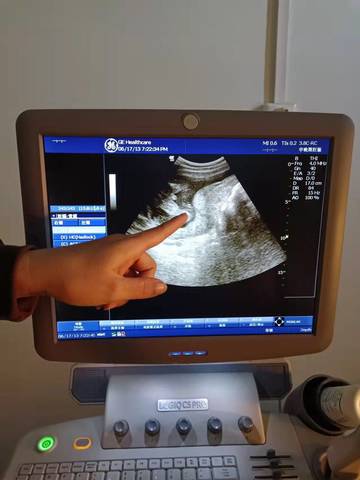

B超截图看看男孩女孩

journal_insert_pic_1687387447journal_insert_pic_1687387462

你好,对于宝宝是男孩女孩虽然很好奇,但是怀孕的单子、数据、表现是判断不出来的,在这也愿你心想事成。

你好。我们是判断不了男宝宝跟女宝宝的,孕期定期检查,我觉得宝宝健康就好的。祝心想事成 。